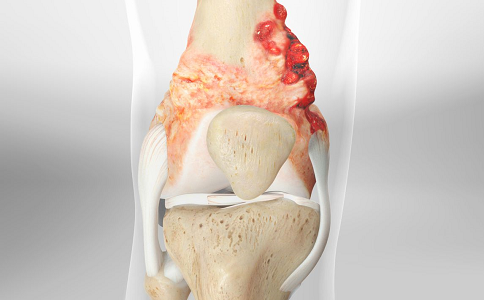

骨肉瘤可以治好吗?事实上骨肉瘤早期由于恶性程度小,尚未发生转移,治好的可能性很大。那么骨肉瘤治疗方法有哪些?骨肉瘤的治疗方法有很多,比如手术治疗、放射治疗和化学治疗,但是手术是治疗几乎所有骨肉瘤的重要部分,主要包括用于诊断癌症的活组织检查和切除肿瘤。

图源:wkhs